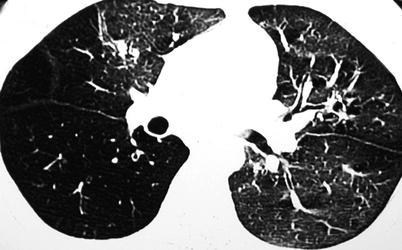

Postinfectious bronchiolitis obliterans (constrictive bronchiolitis or obliterative bronchiolitis) is a clinical syndrome of chronic airflow obstruction associated with inflammatory changes in the small airways as response to epithelial injury associated with infections. It is particularly associated with Adenovirus, RSV, Varicella, and severe Mycoplasma infection. The chest x-ray findings are often nonspecific and can appear normal, but the most common abnormality is hyperaeration (Yalcin et al. 2003). On HRCT, there is a mosaic perfusion pattern (Fig. 13.5). Perfusion is diminished in areas of parenchymal attenuation due to vasoconstriction secondary to hypoxia. Inspiratory and expiratory phases of ventilation are important in HRCT to better assess air trapping in this condition (Hansell et al. 1997). Peribronchial thickening, atelectasis, bronchiectasis, and sometimes lung volume reduction can also be seen. Swyer-James is a subtype of postinfectious bronchiolitis obliterans, which is typically unilateral. It can affect one lung segment, a lobe, or the entire lung. The characteristic chest radiographic and CT findings are hyperlucency due to the pulmonary hypoperfusion, reduction of vascular and hilar markings, and volume reduction of the affected lung or lobe (Daltro et al. 2011) (Fig. 13.6).

Fig. 13.5.

Postinfectious bronchiolitis obliterans. High-resolution CT scan images in expiratory phase demonstrate the typical “mosaic perfusion” pattern